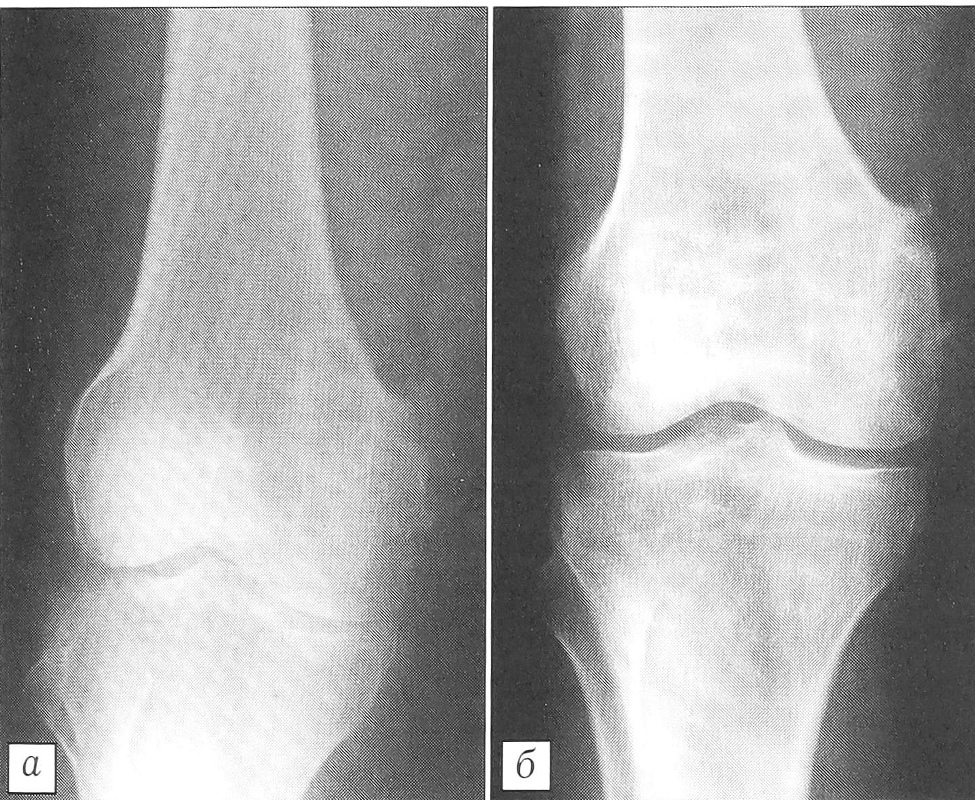

Анализ рентгенограмм показал, что через 1 мес после хирургических вмешательств картина неоднородной «глыбчатой» структуры в местах заполнения дефектов «Остеоматриксом» или в пространствах между его гранулами и аллоимплантатами, выявлявшаяся сразу после операции, полностью исчезала. Рентгеновская тень была практически однородной и имела умеренную плотность (рис. 1). Через 3 мес в большинстве случаев (66%), а через 6 мес у всех больных места, куда помещался «Остеоматрикс», по плотности рентгеновского изображения были неотличимы от окружающей губчатой костной ткани (рис. 2). Признаки перестройки замороженных кортикальных аллоимплантатов, применявшихся совместно с гранулами «Остеоматрикса», во все сроки наблюдения были минимальными (рис. 3), тогда как поверхностно-деминерализованные кортикальные аллотрансплантаты к 6-му месяцу частично инкорпорировались в материнское костное ложе (рис. 4).

Рис. 2. Рентгенограммы больной Т. 41 года. Диагноз: воспалительный процесс в области внутреннего надмыщелка правой бедренной кости.а — после открытой биопсии; б — через 3 мес после операции с пластикой дефекта «Остеоматриксом».